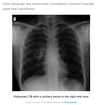

CXR for covid?

• clasically there is bilateral interstitial shadowing typical of viral pneumonia

• takes a long time to resolve - may have persistent shadowing/ fibrosis